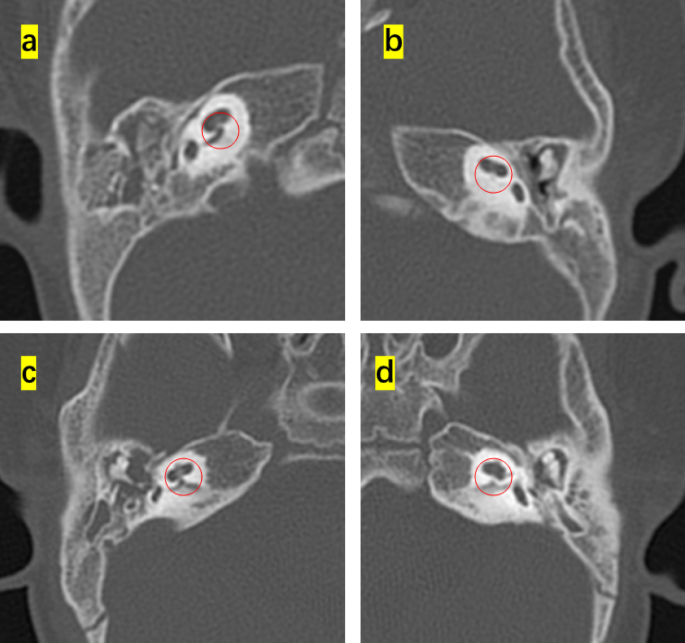

This study enrolled 16 children (8 months to 4 years old) that were diagnosed with diverse phenotypes of syndromic hearing loss and underwent CI. These included six, three, one, and six cases of WS, NS, KS, and CS, respectively. Children with different types of NCP-based hearing loss exhibit unique facial features: the iris of children with WS were heterochromic, and there were no abnormalities in the head and facial structure; the patients with NS had protruding foreheads, widened eye distances, and downward inclination of the eye fissures; the patient with KS had cracks on the long eyelid, with a slight outward rotation of one-third of the lower eyelid and a cup-shaped ear on the right side; all the CS patient were with predominant craniofacial anomalies involving the ears and eyes. Table 1 shows the main clinical features of the 16 children, specifically highlighting the ear malformations and the degree of developmental delay. There were observable differences between the types of syndromic hearing loss. WS and NS showed mild malformations of the middle and inner ear (Figs. 1 and 2). KS (Fig. 3) primarily exhibited malformations of the outer and middle ear structures. CS (Fig. 4) showed significant malformations in the outer, middle, and inner ear and showed varying degrees of stenosis or occlusion of the cochlea in different cases (Fig. 5). Cochlear nerve canal stenosis was observed in almost every CS case. Apart from WS, the other three syndromes showed clear craniofacial malformations, growth delay, and varying degrees of neurodevelopmental delay. Gesell scores were below the normal value of 85. Among the syndromes, WS and NS exhibited mild symptoms, KS showed more pronounced symptoms, and CS cases were the most severe.

Ear CT scans in CHARGE syndrome(CS) cases. (a-c) Developmental abnormalities in the middle and inner ear of CS, including underdeveloped semicircular canals, vestibular malformations, an abnormal facial nerve course, a narrow internal auditory canal, and cochlear apical–middle turn hypoplasia. (d) Ossicular chain abnormalities.